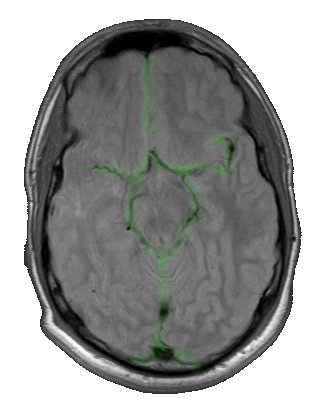

meine MRT Aufnahme : Circulus

Willisii |

Zwei Arterienpaare (A. carotis interna & A. vertebralis)

versorgen das Gehirn mit Sauerstoff und Nährstoffen.Der

Hirnkreislauf kann in ein vorderes und hinteres

Versorgungsgebiet unterteilt werden, die über einen Kreislauf

der Hirnbasisarterien, dem Circulus Willisii

(A. cerebri anterior, A. communicans anterior, A. cerebri

media, A. communicans posterior,

A. cerebri posterior A. basilaris, A. carotis interior),

kommunizieren und multiple Kollateralverbindungen untereinander

aufweisen

Circulus Willisii |

Der vordere Kreislauf wird durch die beiden Halsschlagadern, A

carotides interna und die innerhalb des Schädels gelegenen

Gefäße, Arteria cerebri media und anterior und deren Äste

gebildet.

Der hintere Kreislauf wird durch die Rückenmarkarterien, die

Arterie vertebrales, deren letztes

Segment intrakraniell liegt und die aus den Aa. vertebrales

intrakraniell entstehende Arteria basilaris sowie die davon

abgehenden Arteriae posteriores und von diesen Gefäßen abgehende

Äste gebildet.

Stenosen der hirnversorgenden Arterien kommen besonders häufig

am Abgang der Arteria Carotis interna vor. |